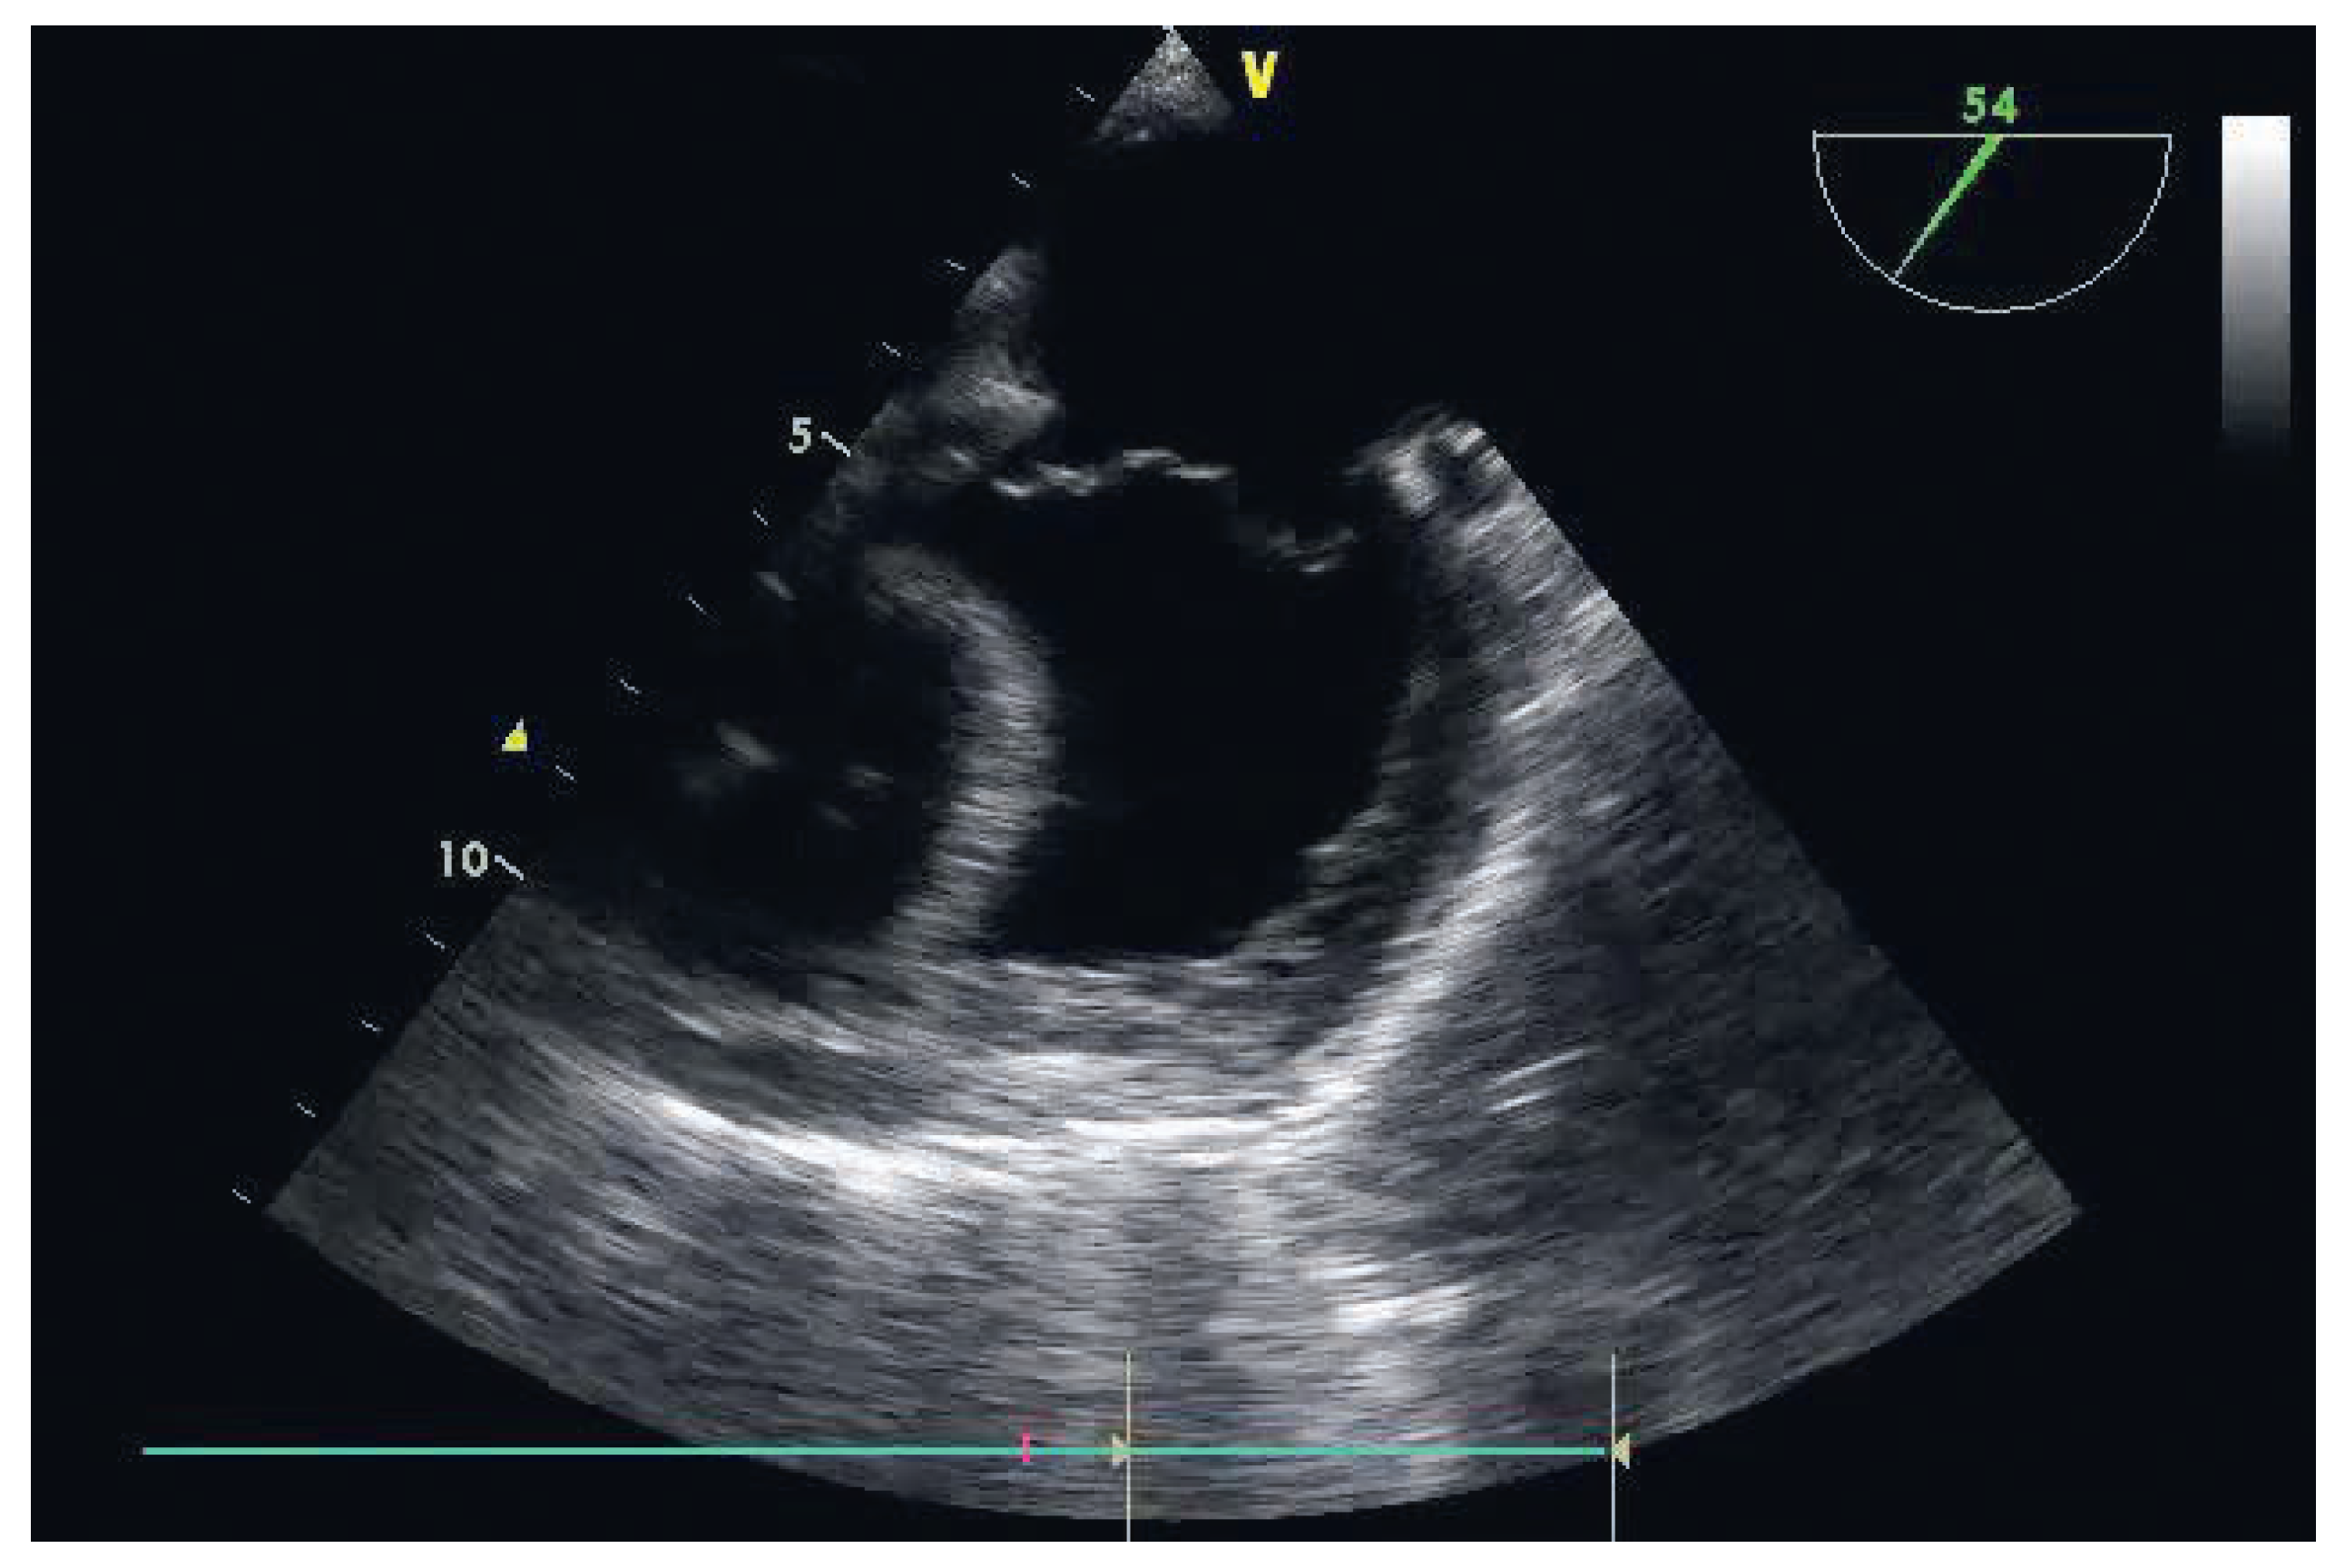

Diagnosis